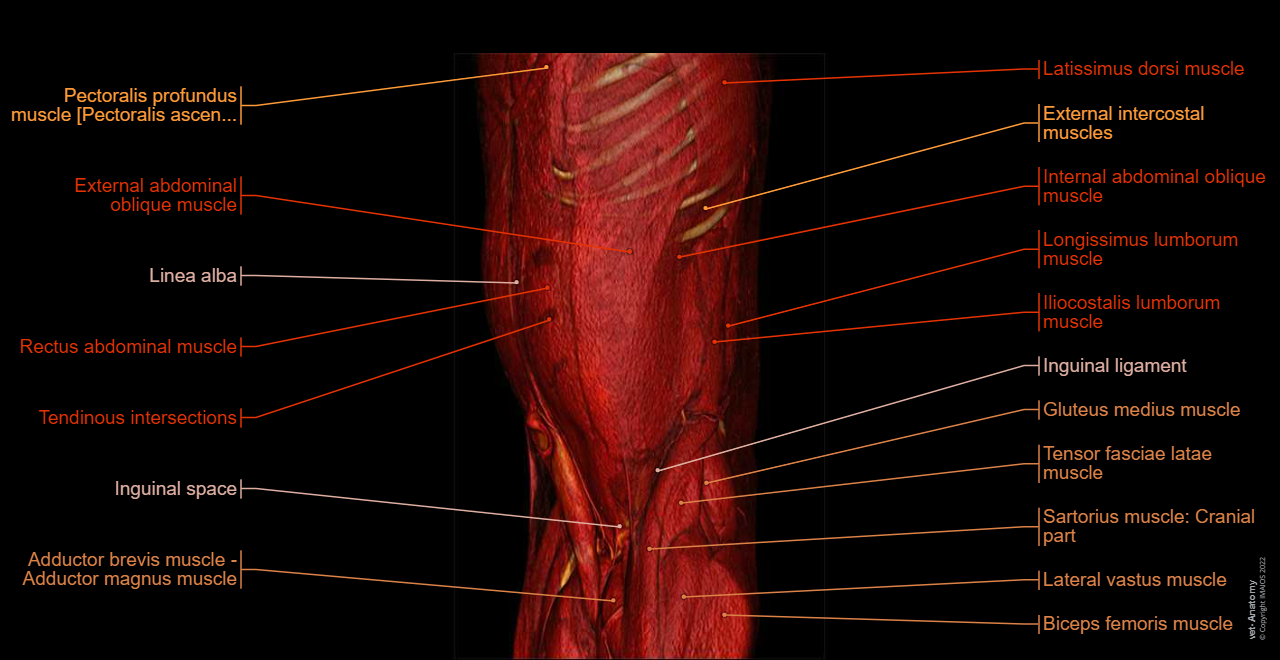

Abdomen and pelvis anatomy of the dog on CT - Anatomy atlas - 3D: Myology - Muscles of abdomen - Muscles of the tail [coccygeal]

Abdomen and pelvis anatomy of the dog on CT